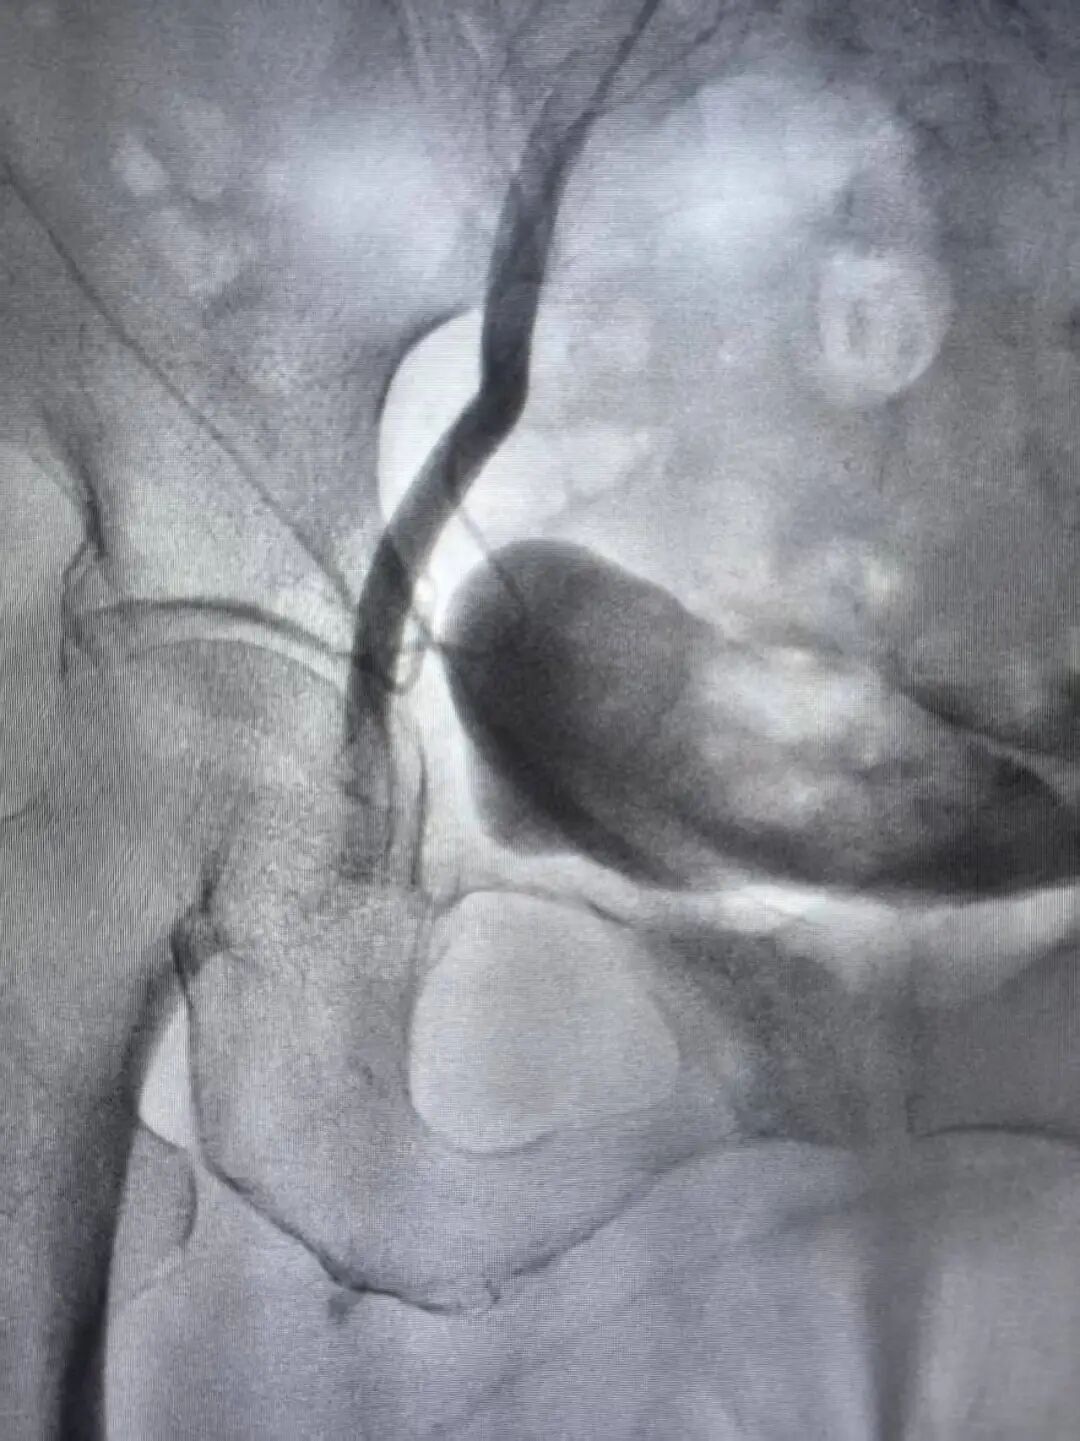

(右侧股总动脉栓塞)

“马上启动多学科协作!”急诊科立即联系介入及脑血管病科薄进保主任。医护团队在最短时间内完成术前准备,患者从急诊室直接推入介入手术室,全程无缝衔接。急诊科护士寸步不离,密切监测心率、血压、血氧;介入团队早已就位,薄主任为孙奶奶实施右下肢动脉血栓取栓术

(介入术后闭塞的血管完全再通)

两个小时后,手术顺利完成。孙奶奶右下肢的皮温、皮色即刻改善,足背动脉搏动恢复,疼痛麻木消失。从入院到血运重建,全程高效顺畅,没有浪费一分一秒。